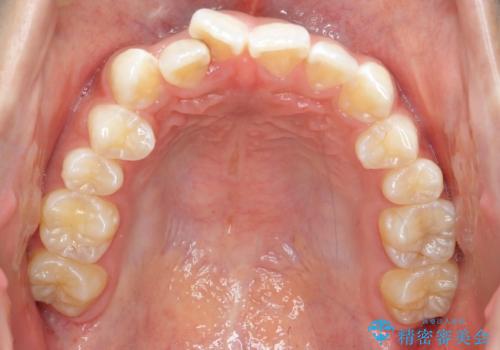

前歯のがたつき 1年かからず治療 マウスピース矯正

- 前歯のがたつきを主訴に来院。

インビザラインで歯を抜かずに並べました。

マウスピースの延長(リファインメント)もなく、短期間で綺麗に並びました。